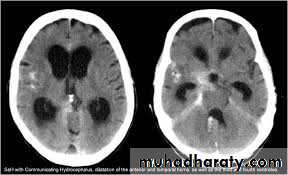

Hydrocephalous

2 types

Obstructive ( non – communicating )

Craniophyrengioma

Medulloblastoma

Ependymoma

Aquiduct stenosis , comments cause of obstruction being congenital in nature .

Non –obstructive ( communicating )

No obstruction of the ventricular pathway , but the absorption of the csf at the level of arachnoids' granulation is occluded secondary to lodge by blood clot or inflammatory cell or infection post meningitis most commonly to occur post SAH .